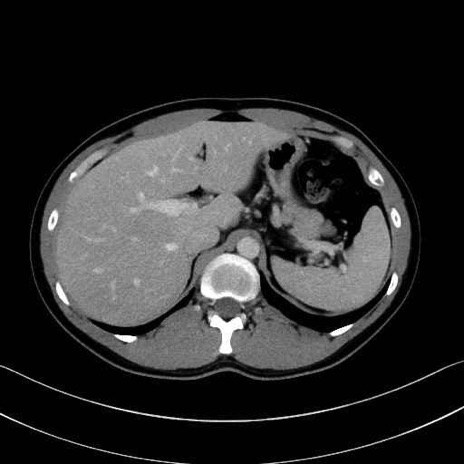

腰方形筋(quadratus lumborum muscle)のCT画像の解剖

1. 体幹部(腹部・背部・後腹壁)の筋肉

腰方形筋 (Quadratus lumborum)